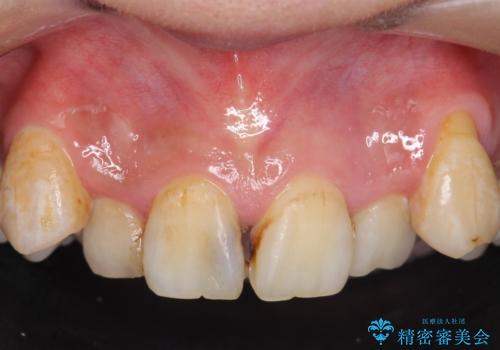

- 上顎前歯の見た目が気になるのでセラミックにしたいといらっしゃった方の症例です。

右上2は歯の神経が死んでおり、根尖病変を認めたため根管治療を行いました。

その後右上1,2番目及び左上1番目の歯に対してオールセラミッククラウンによる補綴を行いました。